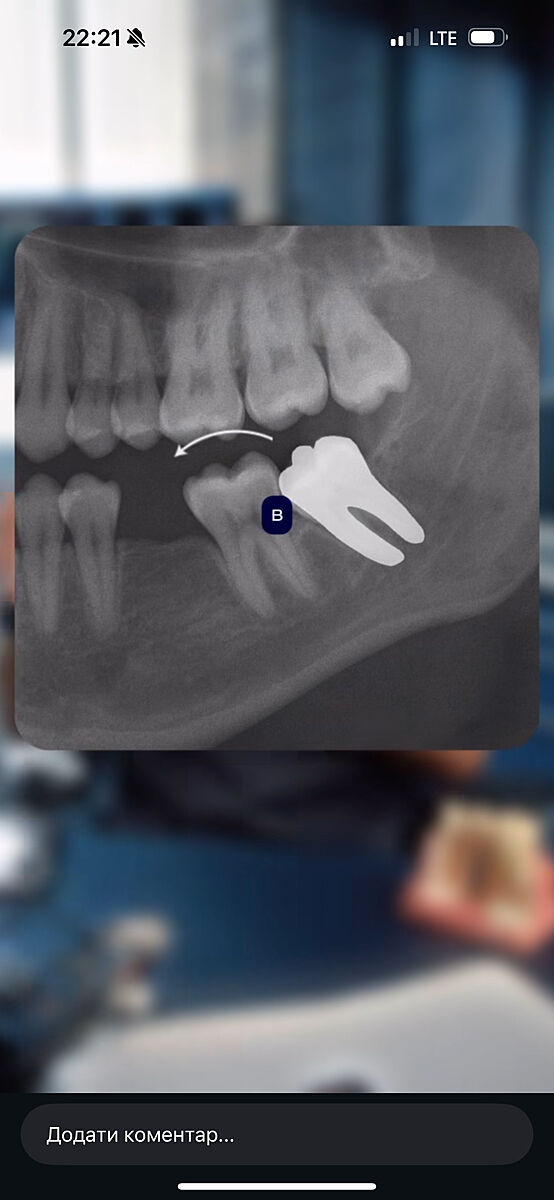

Видаляти зуби мудрості? Фото КТ дитини. Чому ортодонти так хочуть позбутись їх?

В доньки вирівняні зуби брекетами, 14 років

Ортодонт каже треба рвати через 6 міс всі 4 зуба мудрості, поки немає в них коріння, щоб потім не поїхав зубний ряд

Як на мене то верхні зуби ростуть вниз, не заїжджають на сусідні

у вас прямі покази на виривання вони вже прям впираються в зуби

ряд точто поїде як не прибрати

Ще таке фото

Хто знає - прокоментуйте будь ласка